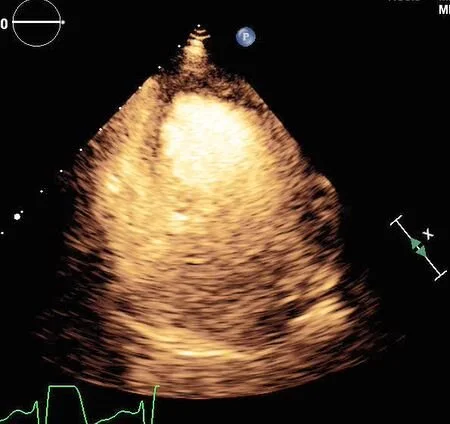

Contrast echo confirms the perfusion defect